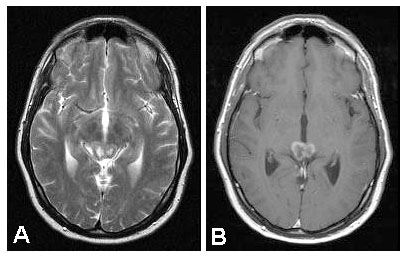

disease. Figure 4.

Further investigations did not substantiate this diagnosis so that

specific treatment was not initiated. One month later, the lesion had

grown further and forced medical consultants to agree to treatment.